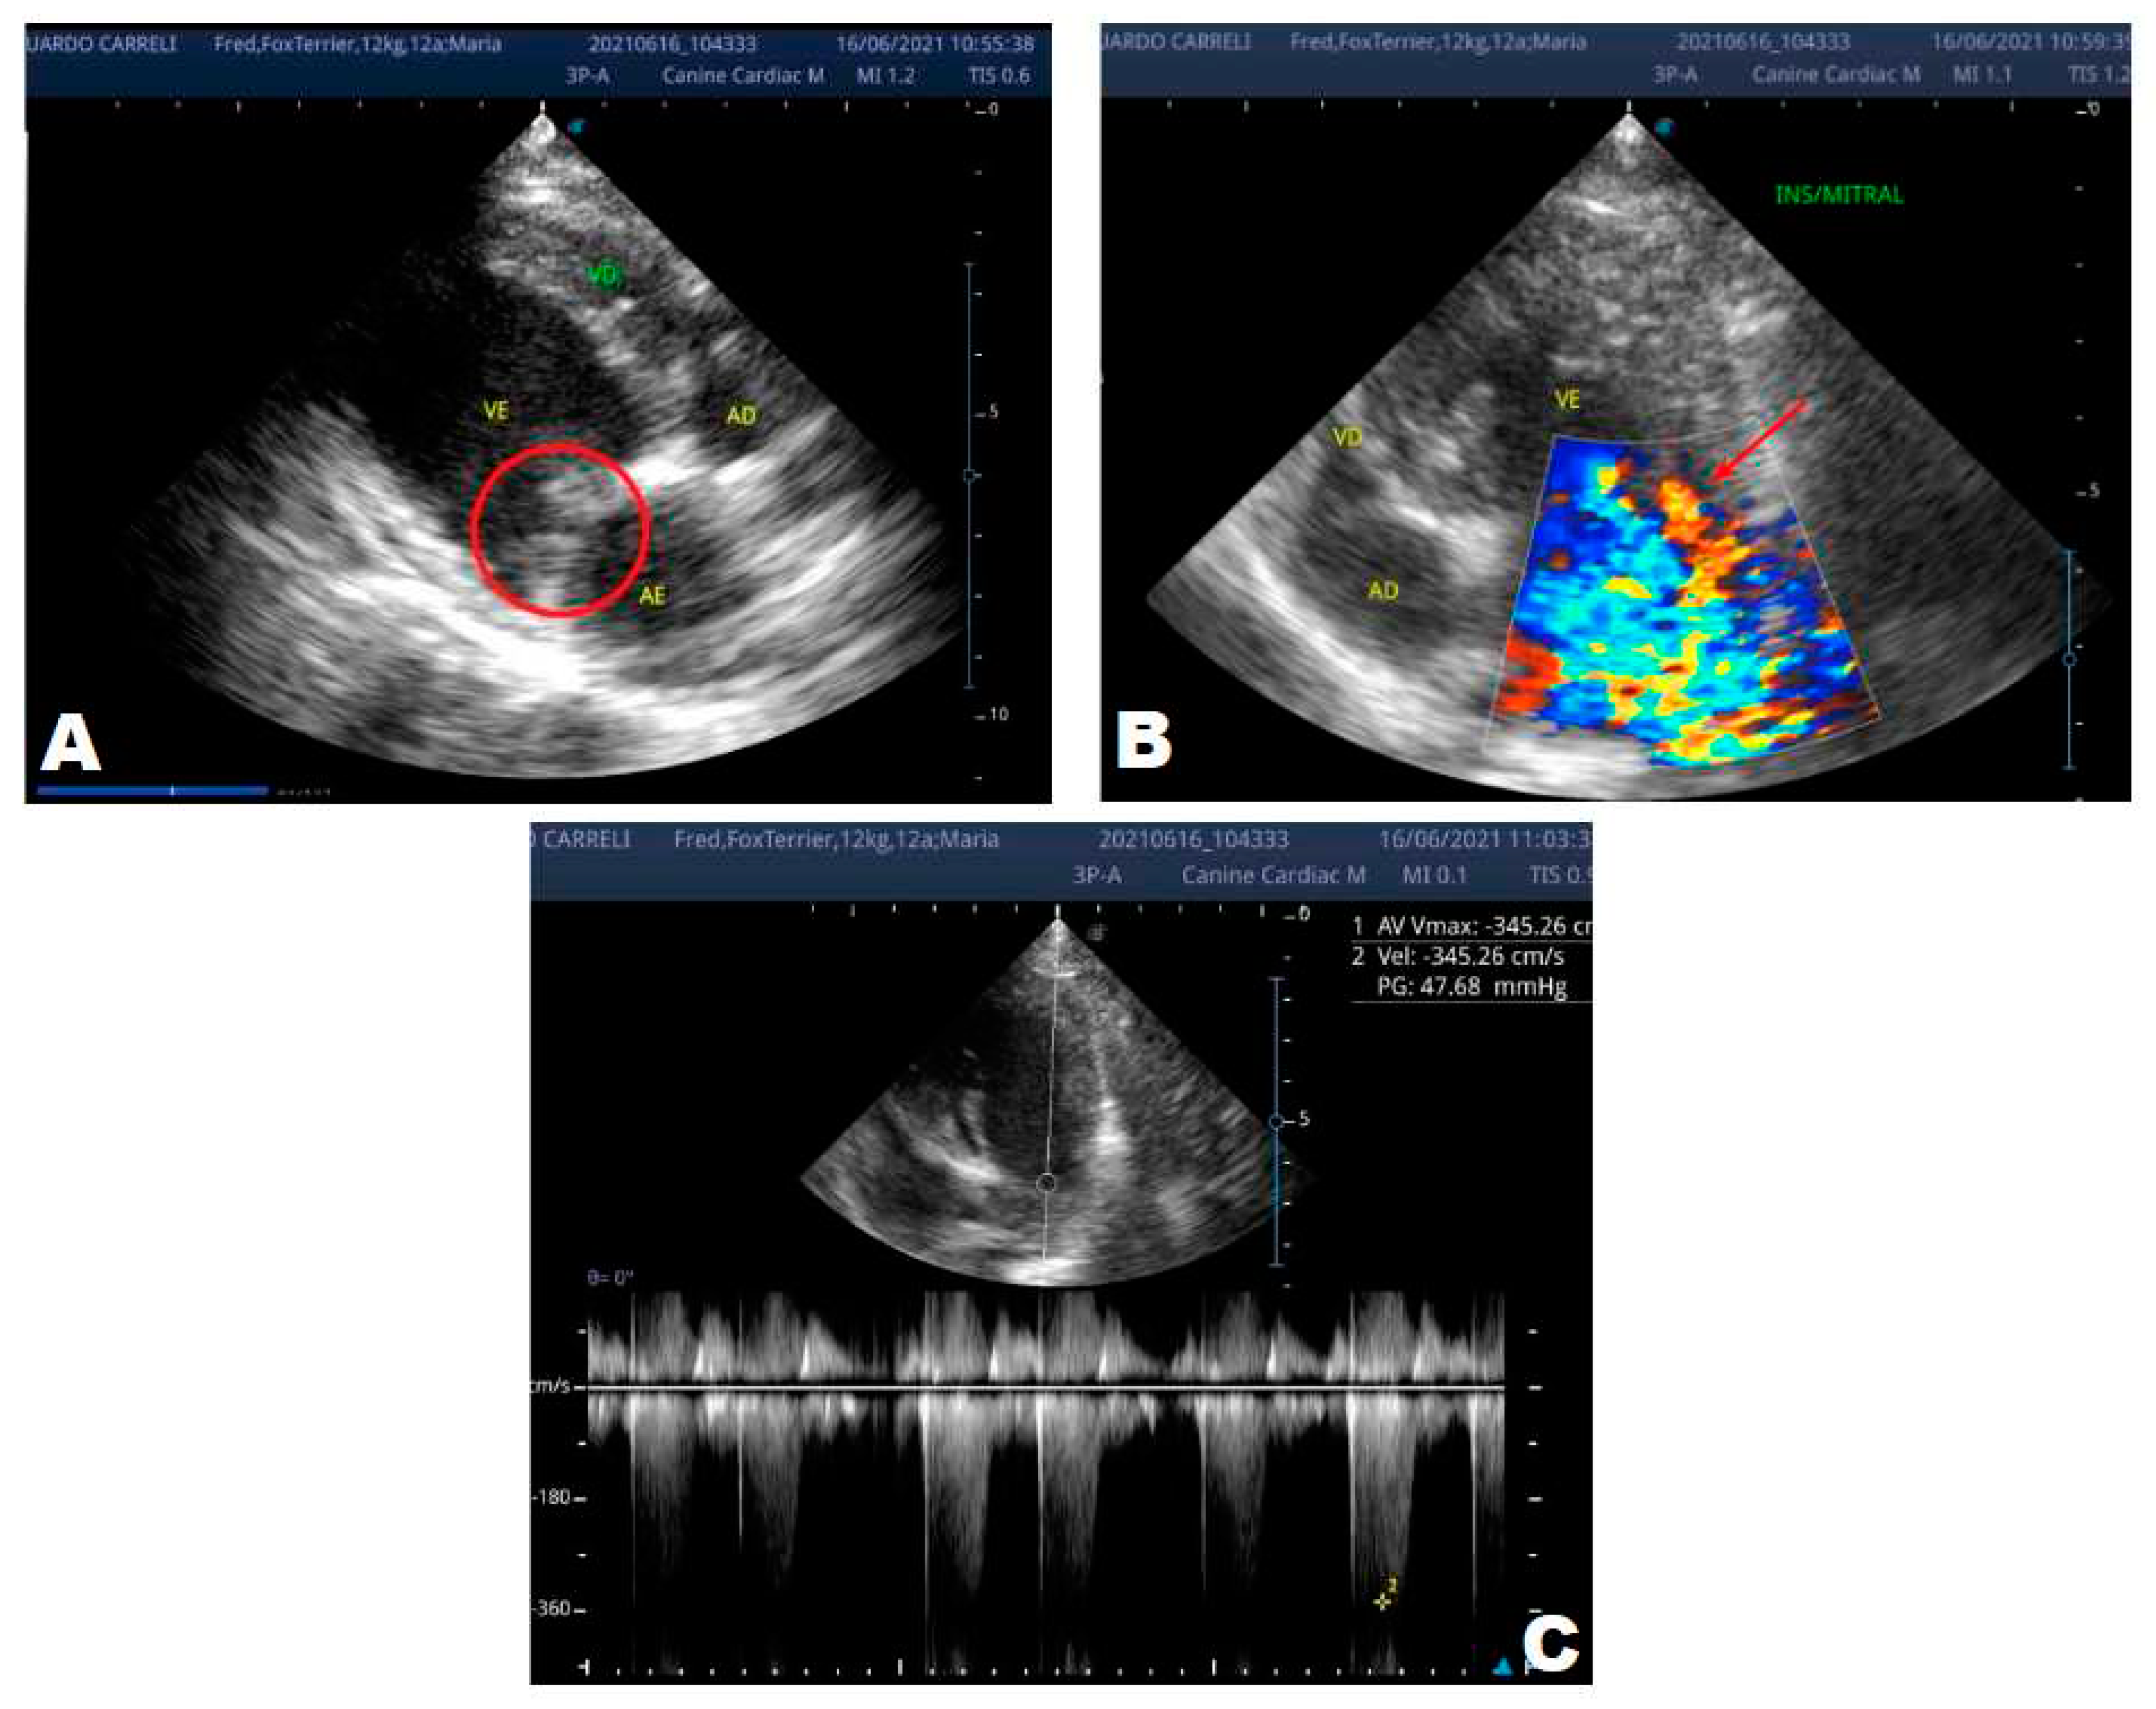

One year later, the animal returned for a new evaluation, repeating the ECHO (Figure 2), which showed the progression of the increase in the left atrium. The electrocardiogram (ECG) (Figure 3) shows baseline sinus arrhythmia with the presence of a premature ventricular complex (Figure 4). Owners reporting drowsiness, hyporexia, and syncope, however, did not present tiredness or cough. Blood pressure was 80 mmHg.

In 2022, one year after the diagnosis, the animal returned for annual control exams. The ECHO showed an increase in the left atrium and ventricle, thickened/degenerated mitral valve (Figure 2), preserved diastolic function, and low probability of pulmonary hypertension; the ECG detected an increase in the duration of the P wave and the QRS complex (Figure 3), suggestive of atrial and left ventricular overload, baseline sinus arrhythmia with the presence of a premature ventricular complex.

Figure 2. Echocardiogram (2022): observed increase in the left atrium and ventricle; thickened/degenerated mitral valve (A); observed in a Doppler study, turbulent systolic flow within the left atrium, characterizing significant mitral valve insufficiency (B); systolic turbulent flow within the right atrium, characterizing mild tricuspid valve insufficiency (C); hemodynamic assessment - maximum velocity gradient mitral regurgitation: 3.51 m/s /49.22 mmHg; observed left ventricular diastolic dimension above normal limits with normal systolic function parameters, characterizing systolic dysfunction; preserved diastolic function.